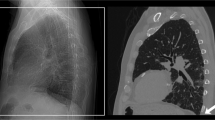

Segmentation and landmarking of computed tomographic (CT) images of pediatric patients are important and useful in computer-aided diagnosis, treatment planning, and objective analysis of normal as well as pathological regions. Identification and segmentation of organs and tissues in the presence of tumors is difficult. Automatic segmentation of the primary tumor mass in neuroblastoma could facilitate reproducible and objective analysis of the tumor’s tissue composition, shape, and volume. However, due to the heterogeneous tissue composition of the neuroblastic tumor, ranging from low-attenuation necrosis to high-attenuation calcification, segmentation of the tumor mass is a challenging problem. In this context, we explore methods for identification and segmentation of several abdominal and thoracic landmarks to assist in the segmentation of neuroblastic tumors in pediatric CT images.

Methods are proposed to identify and segment automatically peripheral artifacts and tissues, the rib structure, the vertebral column, the spinal canal, the diaphragm, and the pelvic surface. The results of segmentation of the vertebral column, the spinal canal, the diaphragm and the pelvic girdle are quantitatively evaluated by comparing with the results of independent manual segmentation performed by a radiologist.